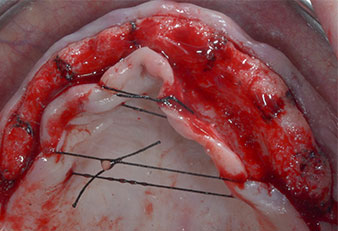

Tre anni dopo era il momento di una protesi dentaria mascellare dello stesso tipo. In base alla pianificazione con CBCT, il rialzo del seno mascellare è stato evitato con l'ausilio di impianti corti e una dima chirurgica è stata utilizzata per trasferire le posizioni pianificate alla cresta alveolare (Figg. 1 e 2).

Uno strumento piezoelettrico (Piezomed I1) a forma di fiamma, rivestito in diamante, è stato usato per contrassegnare le posizioni dell'impianto e per eseguire una preparazione pilota (Fig. 3). Si è prestato attenzione a utilizzare un movimento verticale ascendente e discendente, con potenza ridotta, irrigazione completa e bassa pressione (inferiore a 300 g). Successivamente è stato applicato uno strumento pilota (Piezomed I2A/I2P) per l'ingrandimento iniziale delle sedi dell'impianto del diametro di 2 mm (Fig. 4), seguito da un inserto da 3 mm (Fig. 5).